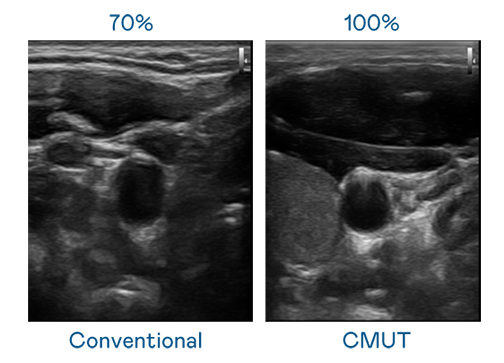

CMUT 技术是一种用电容式微机电元件来产生超音波讯号的技术。与传统 PZT 压电式技术相比,CMUT 频宽增加 30%,更宽频的超音波讯号让影像解析度大幅提升,是实现高影像品质医疗超音波扫描、促进精准医疗发展的关键技术。

大频宽带来超清晰影像

超音波影像的解析度高低,首先取决于探头能发出的讯号频宽。mansion88·明升 CMUT 可提供高清晰的超音波讯号,提供高频宽、高灵敏度、影像纹理细节更高的超音波影像,协助医护人员缩短影像判读时间及利用精准的医疗影像进行诊断。